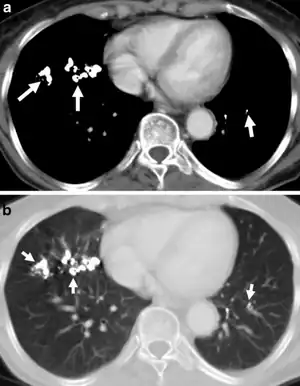

a.b) Barium aspiration images

Barium has a high radio-opacity and the disease may develop after few months of exposure. Extremely dense, discrete small opacities of 2–4 mm diameter, sometimes of a star-like configuration, are seen on the radiograph. Their distribution is uniform. When they are very numerous, superimposition may give the impression of confluency, but this does not seem to occur in reality. The hilar lymph nodes can be very opaque but not enlarged. After cessation of exposure, there is a gradual clearing of the opacities.

The barium particles can be seen as opaque shadows on the chest X-rays of people with baritosis. However, being a benign condition, it neither interferes with lung function nor causes symptoms other than a mild cough.